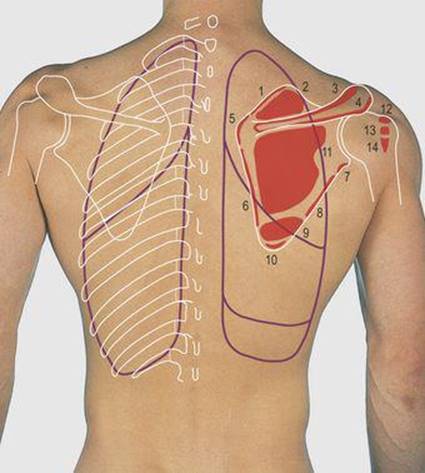

4.7 Posterior chest wall: muscle attachments

1 Letvator scapulae

2 and 12 Supraspinatus

3 Trapezius

4 Deltoid

5 Rhomboideus minor

6 Rhomboideus major

7 Long head of triceps

8 and 14 Teres minor

9 Teres major

10 Latissimus dorsi

11 and 13 Infraspinatus

4.9 Posterior chest wall: ribs, lungs and pleura

1 Spine of first thoracic vertebra

2 Floating ribs (11 and 12)

3 Pleural markings

4 Lung markings

5 Oblique fissure

6 Posterolateral thoracotomy incision

7 Vertebra prominens

Posterior thorax (Fig. 4.7), pleura and lungs (Figs 4.8, 4.9)

The lower three cervical, and all the thoracic, vertebral spines are palpable in the midline. The spine and acromion of the scapula are subcutaneous and its upper, lower and medial angles can be observed and palpated during arm movements. In the anatomical position, the scapula overlies the second to seventh ribs on the posterolateral aspect of the chest wall. Laterally it articulates with the clavicle and humerus but has no medial bony attachment, being free to move over the chest wall in movements of the upper limb (Fig. 7.16, p. 70). Much of the rib cage is impalpable posteriorly, being covered by powerful erector spinae muscles alongside the midline and the scapula and its muscle attachments more laterally. The 11th and 12th (floating) ribs articulate with their respective vertebrae but are free laterally and these ends can be palpated and this mobility confirmed.

The trapezius and latissimus dorsi muscles have attachments to the trunk. Their prime function is in movement of the shoulder girdle; they are considered in Figure 7.16 (p. 70). The deltoid muscle forms the rounded contour of the shoulder, gaining attachment from the clavicle and the scapula (Fig. 7.10, p. 67).